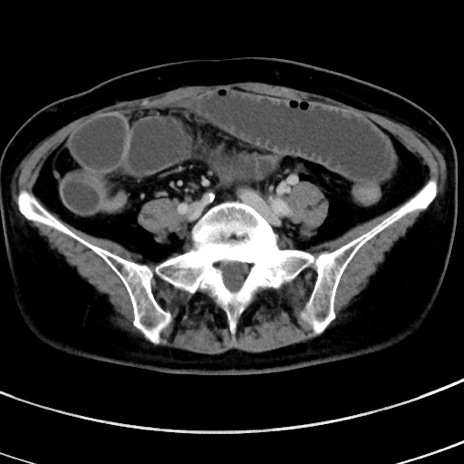

冠状断像

【症例】 60歳代女性

【主訴】むかつき、みぞおちの痛み

【現病歴】3日前よりむかつきがあり、食事がとれない。

【既往歴】糖尿病

【身体所見】発熱なし、心窩部圧痛軽度あるも、腹膜刺激症状なし。

【データ】WBC 7400、CRP 1.92